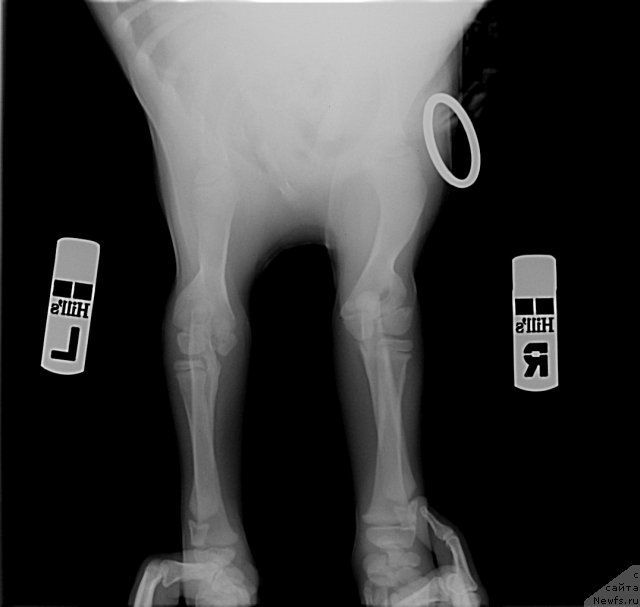

Посмотрите на суставы 2-х месячного щенка лабрадора. Насколько большие ростовые зоны. Какие огромные расстояния между костями суставов. И насколько еще не сформированны суставы. Особенно локтевые. А это собака гораздо легче ньюфаундленда. На него просто наступила сука. И такие травмы.

Фотография № 116289

Фотография № 116290

Фотография № 116291